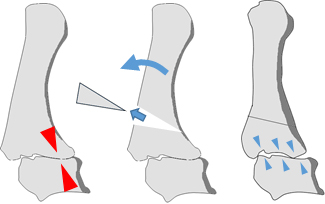

中手骨外転対立位骨切り術は中手骨をつまみやすい位置になるよう骨切りを行います。関節温存が可能でピンチ力も期待できます。一方、重症な母指CM関節症には適応がありません。

- ▼中手骨外転対立位骨切り術

中手骨を背側方向に骨切りし、CM関節掌側の荷重を背側に分散させることで痛みが少なくなることが期待できます。手術後2週間程度の外固定が必要です(手術前後のレントゲン)